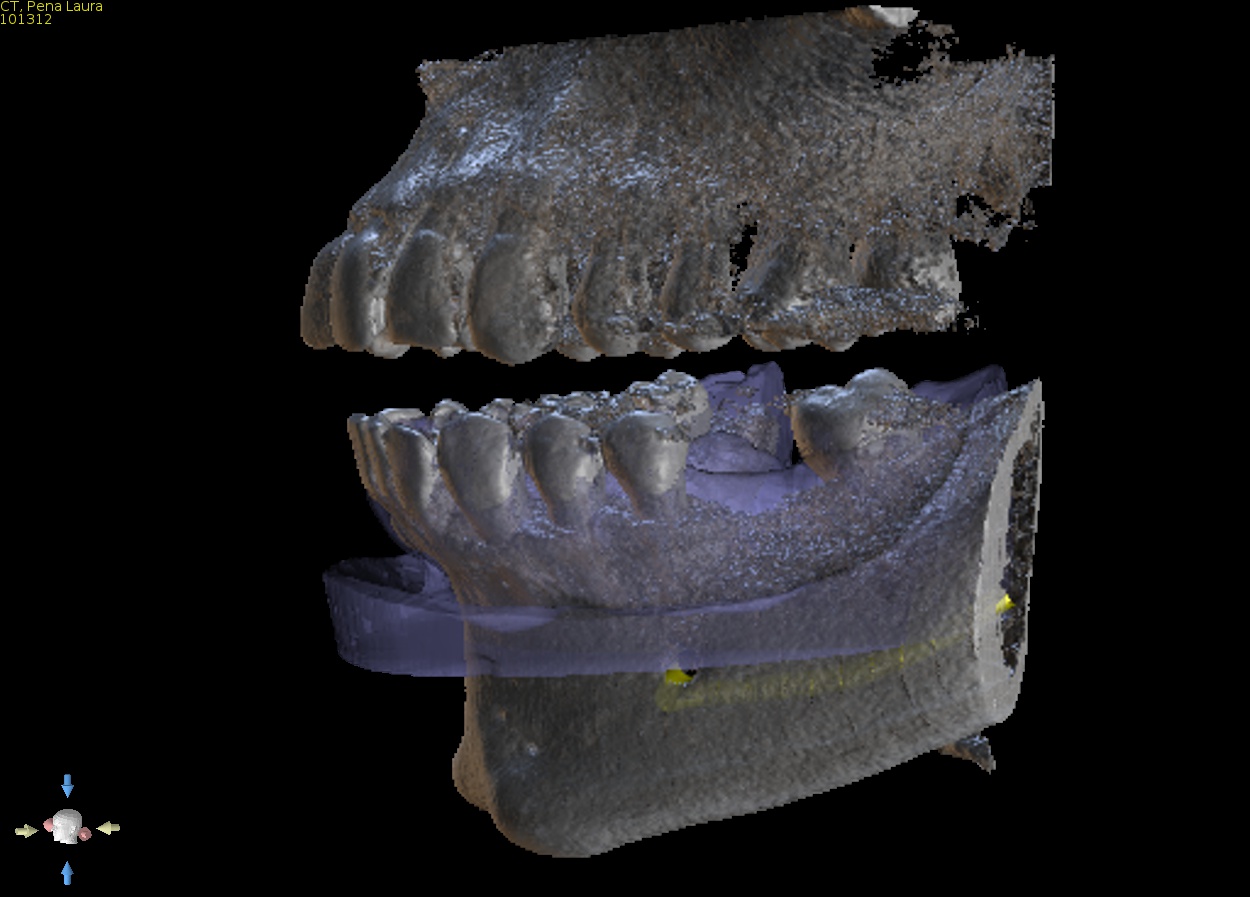

4. Select guide type

5. Guide fabrication

We use state of the art FDA and TGA approved, fully tested and calibrated 3D printing machines and materials for our surgical guides. You will receive a perfectly fitting sturdy guide with drill tubes precision fitted ready for use. All guides are manufactured in Sydney, Australia at our own dedicated facility so fast turnaround is always guaranteed. Rush orders are usually not an issue.

We will supply a drill guide with drill tubes suitable for your selected type of guide.

We can also supply genuine implant manufacturers drill tubes when requested.

Various types of guides are available for you to select. All can be tooth borne, tissue borne bone supported* or a combination of each. * Bone supported guides are dependant on CBCT quality.